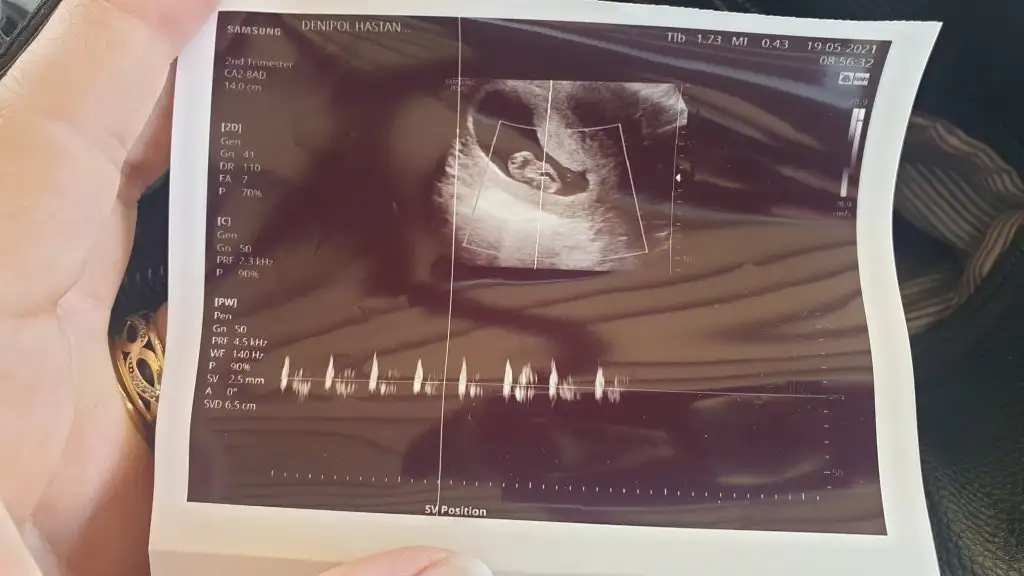

karından ultrasın 9+4 :)

Eklentiler

• 20210519_093816.webp

26,1 KB · Görüntüleme: 62